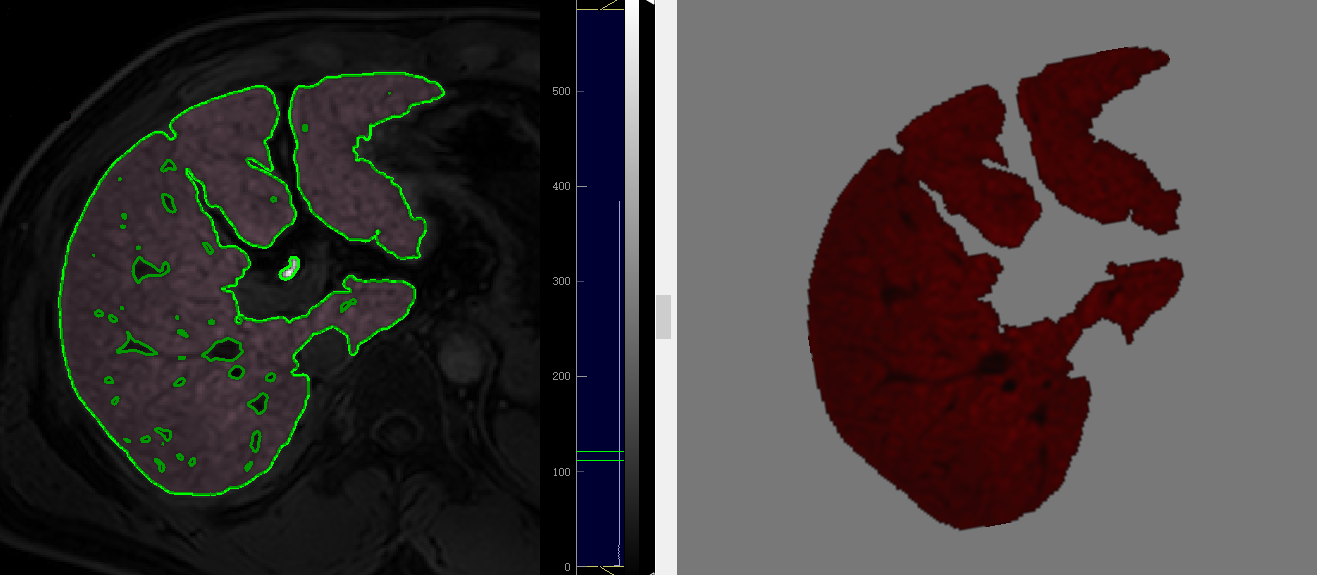

Demonstration of radiomics analysis on Gadoxetic acid-enhanced hepatobiliary phase (HBP) axial MR image at hepatic portal level in a 54-year-old man with hepatitis B–related liver cirrhosis.